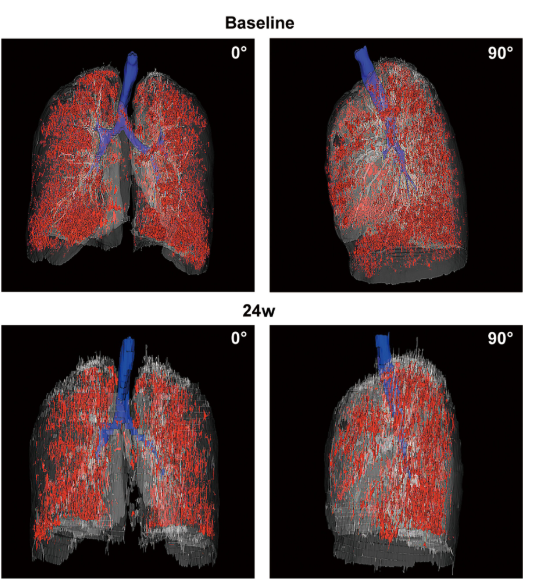

影像學(xué)檢查:對于患者 #2902,定量分析顯示基線(xiàn)時(shí)總體肺氣腫面積比為 12.75%,移植后 24 周降至 10.02%。在患者 #8009 中,肺氣腫面積比值從基線(xiàn)的 10.85% 下降到移植后 12 周的 9.08%。CT 圖像的三維可視化顯示,肺氣腫的減輕在下葉比在上葉更明顯。

患者 #2902 自體 P63 細胞移植前和后 24 周連續肺部 CT 圖像的三維可視化。

結論:干細胞治療24周后,慢阻肺患者的肺功能指標、影像學(xué)檢查、生活質(zhì)量和運動(dòng)功能均得到改善,且未發(fā)生腫瘤或其他嚴重不良事件。可以達到干細胞治療慢阻肺短期療效的結果。